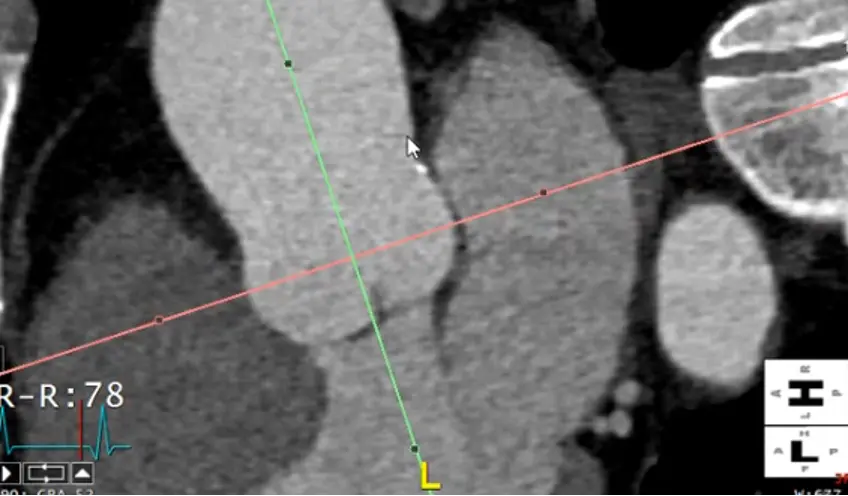

Measure the proximal descending thoracic aorta

- Note: the proximal descending thoracic aorta begins immediately distal to the great vessels (not when the aorta physically starts descending), i.e. after the takeoff of the L subclavian artery

- Line things up in two of the views. In the example Adam showed, he lined it up in the axial and sagittal views and made the measurement in the coronal view.

- Note: the shape of the proximal descending thoracic aorta will not be perfectly circular.